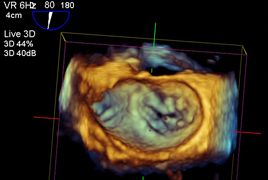

An unserer Klinik führen wir jährlich rund 1500 intraoperative und intensivmedizinische transösophageale Echokardiographien durch. Hierbei kommen sowohl die 2D als auch die 3D Echokardiographie regelmäßig zum Einsatz.